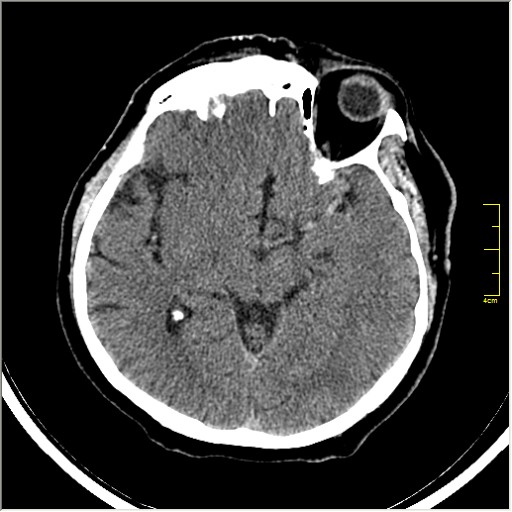

Этот признак называется [Dense MCA sign]; за счёт наличия тромбоза в её просвете. Этот признак является одним из ранних указующих КТ признаков при ишемическом инфаркте головного мозга. Более подробно об этом вы можете прочитать здесь: http://www.radiologyassistant.nl/en/483910a4b6f14.

Ну и для полноты картины, привожу контрольные КТ сканы выполненные через 24 часа: